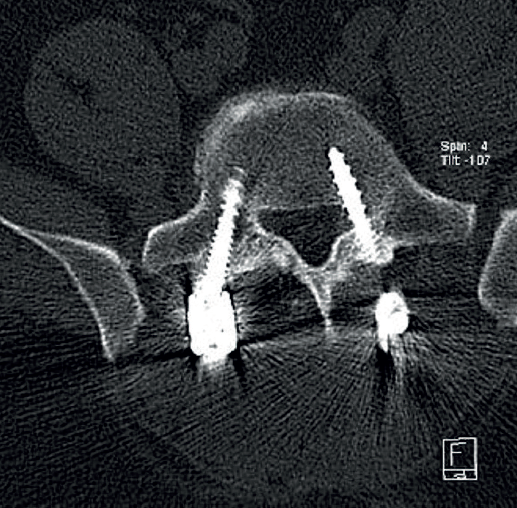

Figura 3. Radiografías del fémur izquierdo. A: proyección anteroposterior, con lesión ósea permeativa en la diáfisis femoral con reacción perióstica; B: proyección lateral, con irregularidad cortical y masa de las partes blandas adyacente, sugestiva de lesión tumoral.